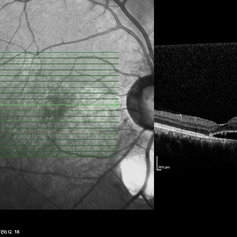

Coloboma of Disc & Choroid

Coloboma of Disc & Choroid

Oct 6 2012 by Hamid Ahmadieh, MD

OCT image of a 25-year-old woman with a small coloboma of choroid associated with coloboma of disc.

Photographer: Hamid Ahmadieh, MD, Ophthalmic Research Center, Labbafinejad Medical Center, Shahid Beheshti University of Medical Sciences

Imaging device: Heidelberg Spectralis

Condition/keywords: coloboma of choroid, coloboma of optic disc, optical coherence tomography (OCT)